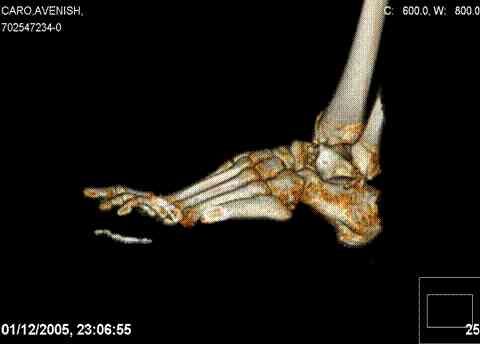

ya by popytalsya sobrat talus anatomichno,seichas pozdno operirovat iz za oteka,po etomy distrakziya apparatom budet optmalna.Posyalu vam podobyai moi sluchai.

14 years old girl

Fall from height ( 3rd floor)